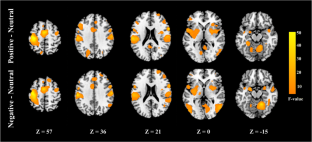

Numerous functional magnetic resonance imaging studies have been conducted to elucidate emotion processing of patients with bipolar disorder (BD), but due to different inclusion criteria used, especially for the history of medication use, the results for euthymic BD patients are inconsistent. For this reason, brain functional effects of psychopharmacological treatments on BD patients have been investigated by numerous fMRI studies, but there is no existing report for brain functional effects of different mood stabilizers. In this study, we compared the emotion processing in BD patients treated by two popularly used mood stabilizer, lithium (N = 13; 30 ± 9 years) and valproate (N = 16; 33 ± 8 years), as well as healthy controls (HC; N = 16; 29 ± 7 years). Two emotional tasks were applied in this study: one used emotional pictures of everyday objects and scenes, and another used emotional facial expression pictures. The main findings were that BD on lithium showed increased fMRI activation in the right dorsal anterior cingulate cortex and bilateral lingual gyrus in response to the positive pictures relative to neutral pictures compared with BD on valproate and HC. Besides, no abnormal activation was observed in the amygdala. Limitations of this study comprise the small sample size and the cross-sectional design. Therefore, the results were suggestive of a different effect of lithium and valproate on brain activities during emotion processing but no causal role can be proposed. The enduring impairments in euthymic state could provide clues to the brain regions involved in the primary pathology of BD.

Fig. 1